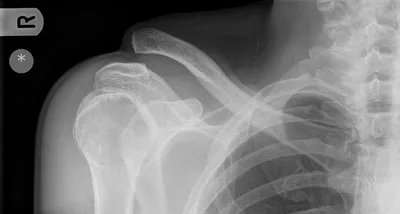

ACJ Radiology Images

This collection contains 1 radiology images related to acj, including various imaging modalities such as X-rays, MRIs, CT scans, and ultrasound images commonly used in medical diagnosis and education.